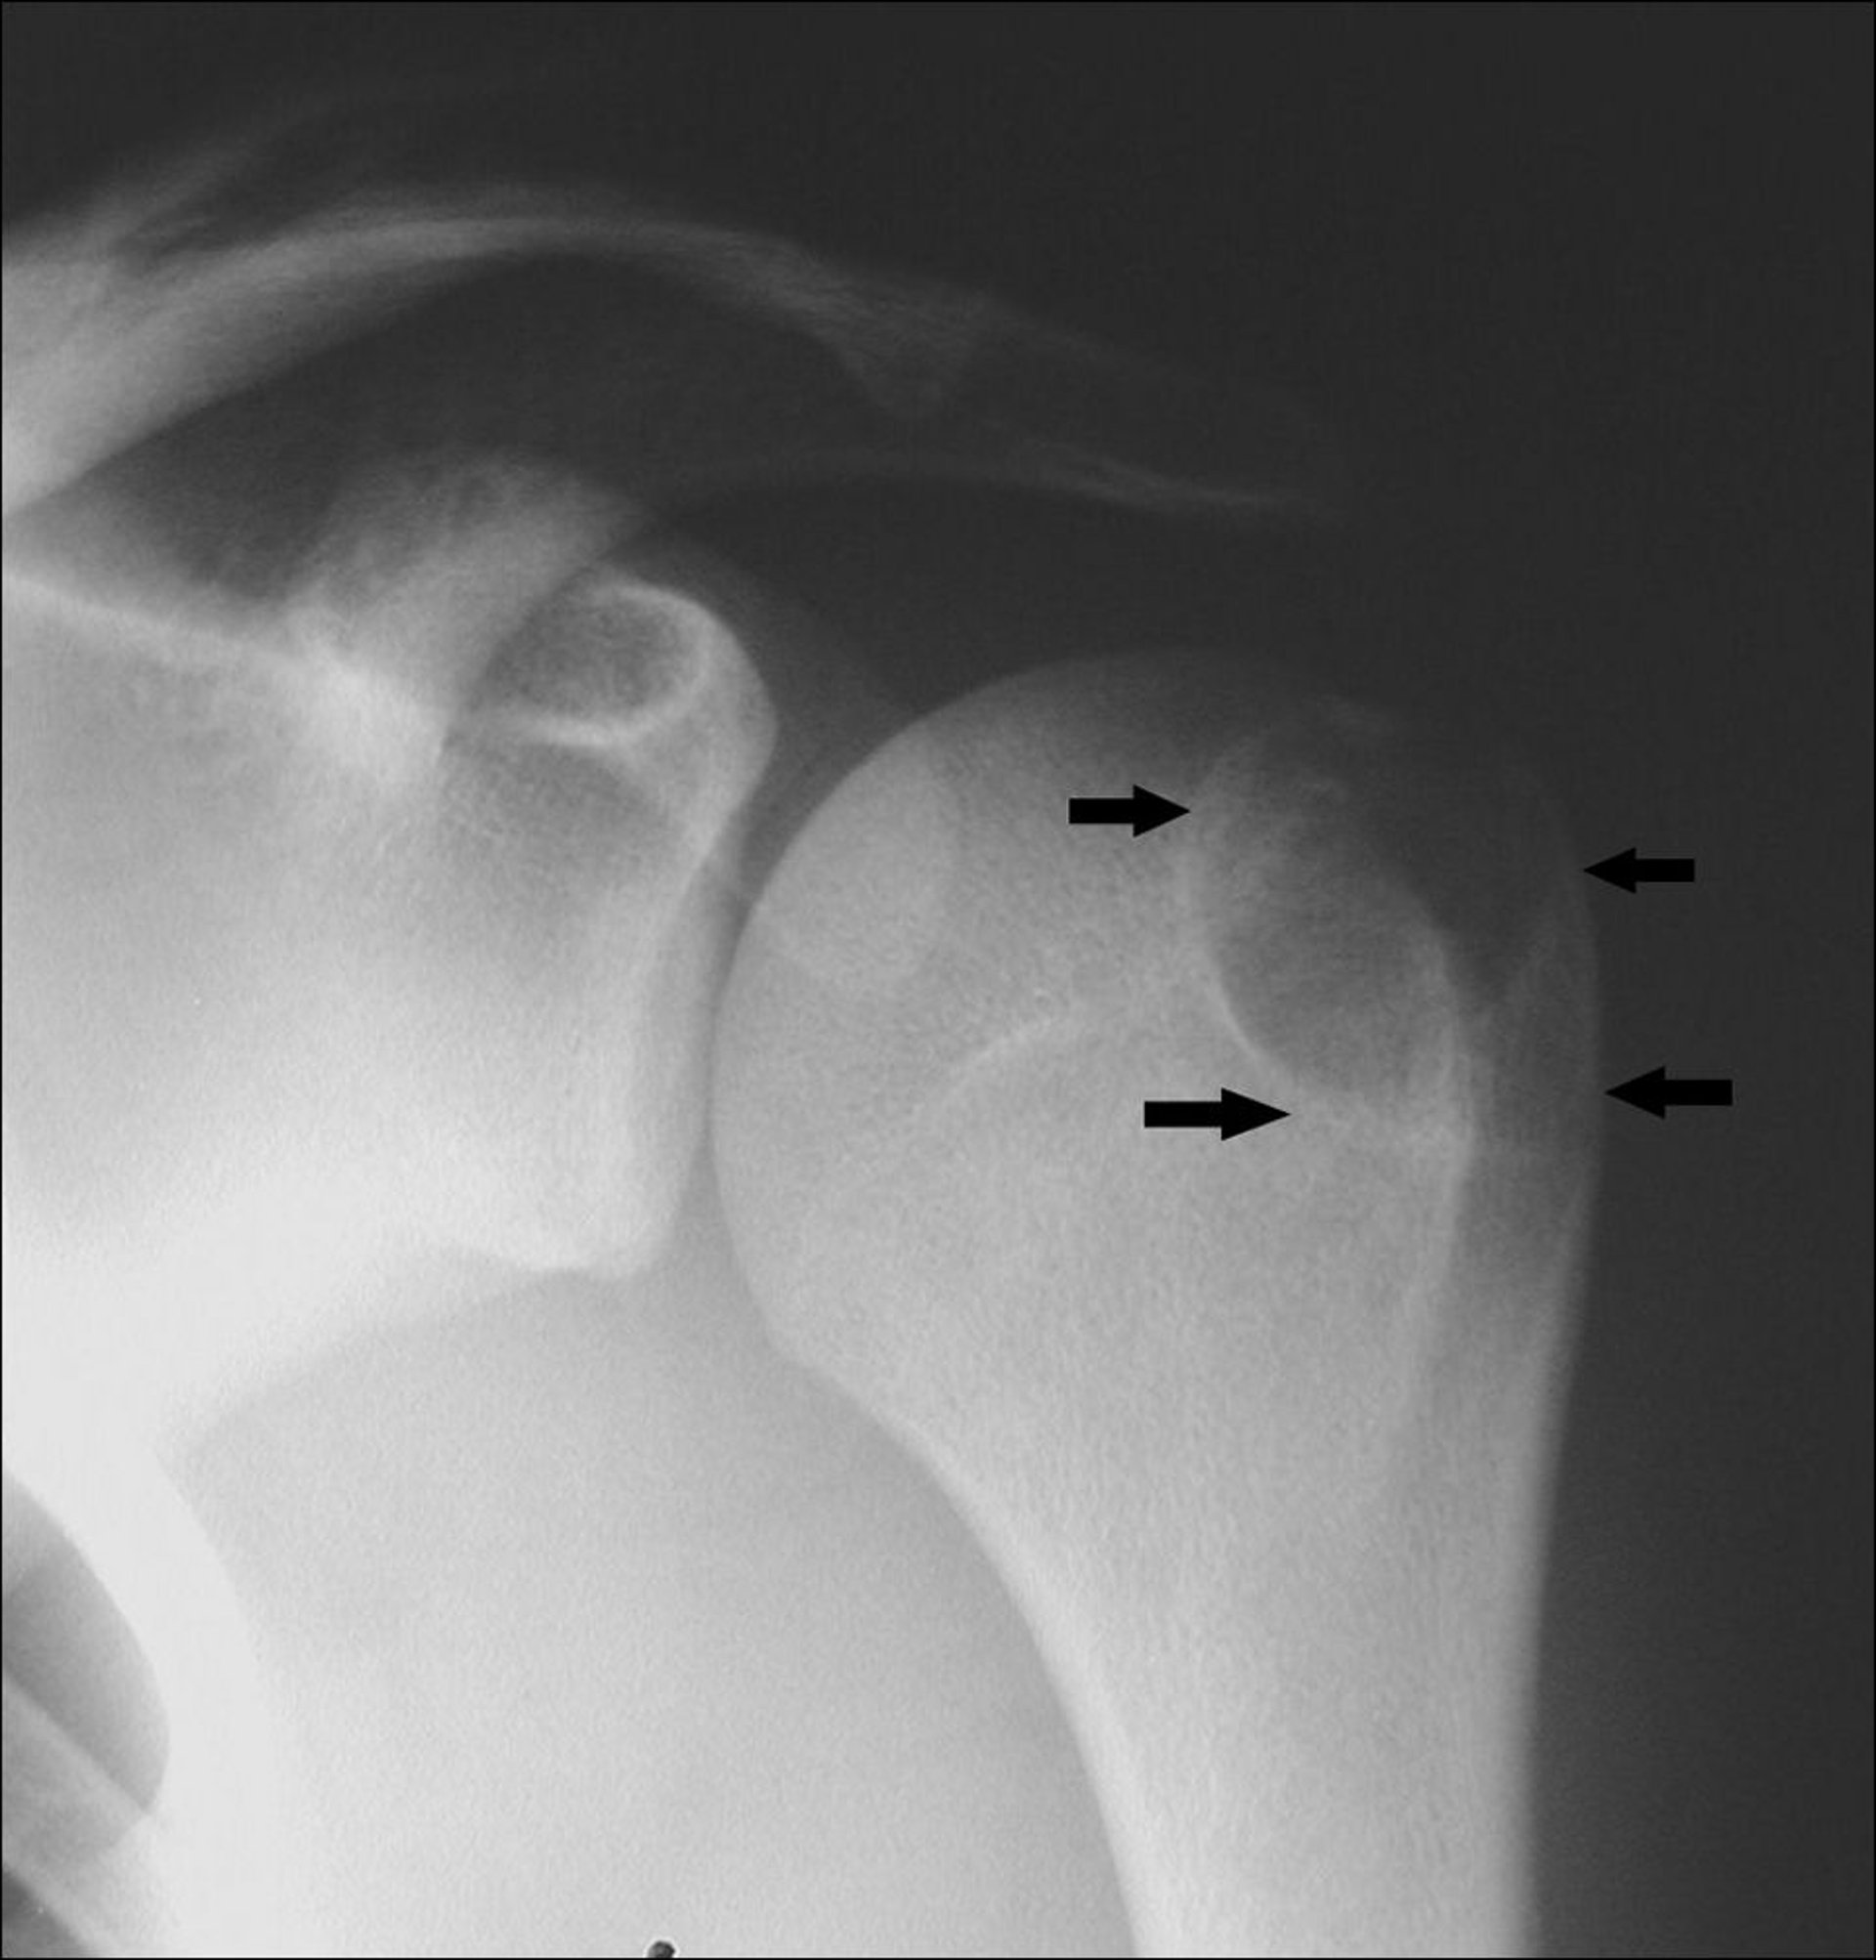

تُظهر هذه الصورة بالأشعة السينية ورمًا ليفيًا غير معظم (اتجاه الأسهم) فوق الركبة في عظم الفخذ.

جرى استخدام الصورة بعد موافقة أصحابها Michael J.Joyce, MD, and Hakan Ilaslan, MD.